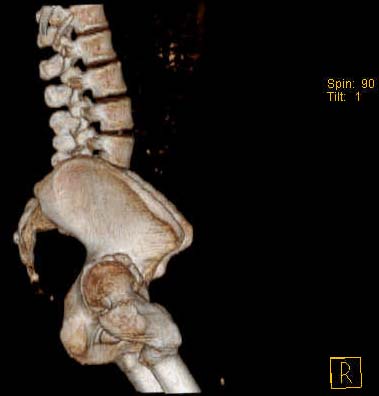

Уважаемые коллеги!Женщина, 35 летВ прошлом по поводу врожденного вывиха бедра перенесла операцию остеотомии по Шанцу

с удлинением правой ноги за счет бедра на уровне диафиза. В последнее время прогрессируют боли в правом тазобедренном суставе, порочное положение правой ноги, затруднена ходьба.Вопросы:1) Целесообразно ли эндопротезирование правого тазобедренного сустава?2) Целесообразный ли следующие действия: канал бедренной кости предполагаем вскрыть для введения ножки протеза на высоте угловой деформации, предполагаем низведение большого вертела с мышцами; протез будет подобран индивидуально, предполагается умеренная версия?В приложении рентгенограммы и трехмерная КТ.В цветном и более качественном варианте КТ размещена здесь